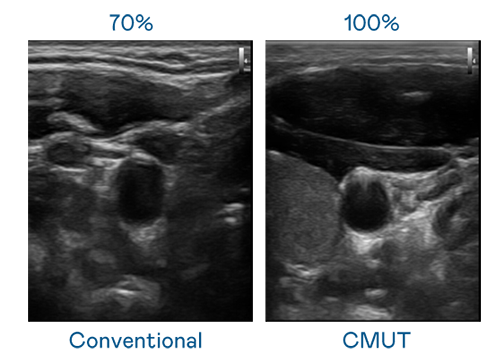

CMUT 技术是一种用电容式微机电元件来产生超音波讯号的技术。与传统 PZT 压电式技术相比,CMUT 频宽增加 30%,更宽频的超音波讯号让影像解析度大幅提升,是实现高影像品质医疗超音波扫描、促进精准医疗发展的关键技术。

大频宽带来超清晰影像

超音波影像的解析度高低,首先取决于探头能发出的讯号频宽。FUN88乐天 CMUT 可提供高清晰的超音波讯号,提供高频宽、高灵敏度、影像纹理细节更高的超音波影像,协助医护人员缩短影像判读时间及利用精准的医疗影像进行诊断。